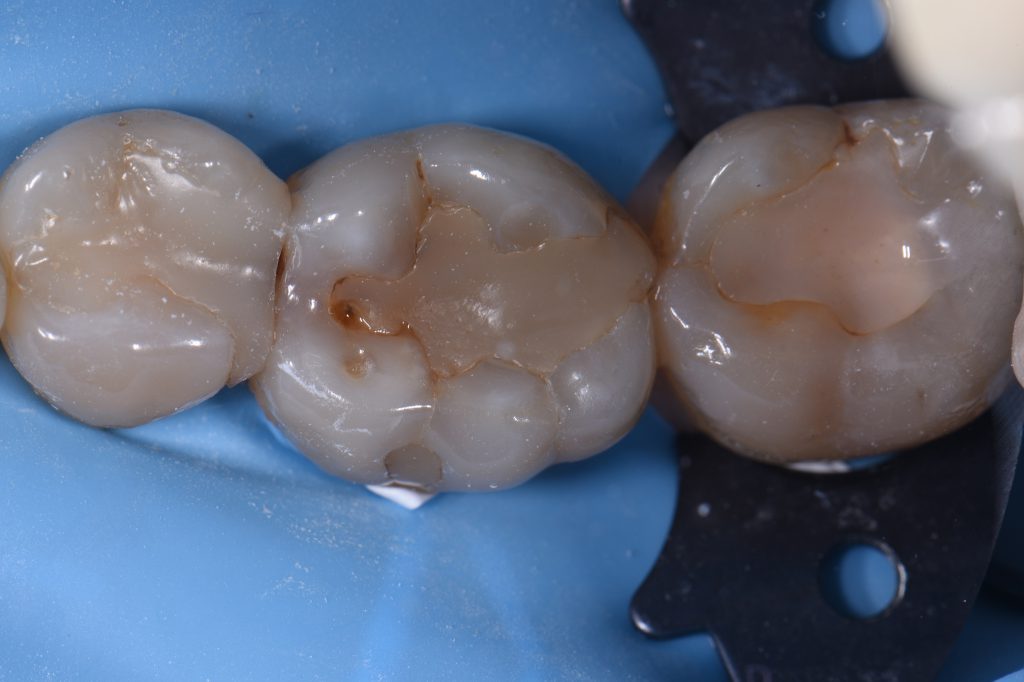

Here we had back to back Class II restorations with some marginal ridge hairline fracture removals.  The mesial of 46 is completely stained and features arrested caries from a roughened wall and gouges from past iatrogenic damage and will need to be addressed at some stage in the future.  Radiographically looks decent.  Should have smoothed it as much as possible before the 45DO, but I was thinking I should just prep it.  Next time.

Flowable liner increments: Kulzer Venus Pearl HKA2.5

Composite: Kulzer Venus Pearl A2.5